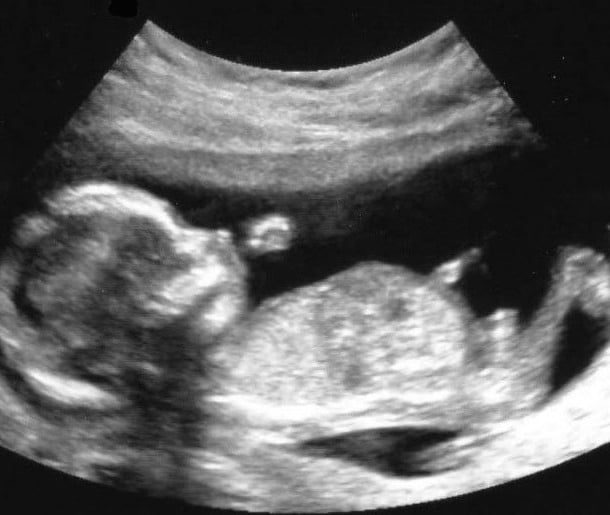

13 haftalık gebelik süreci